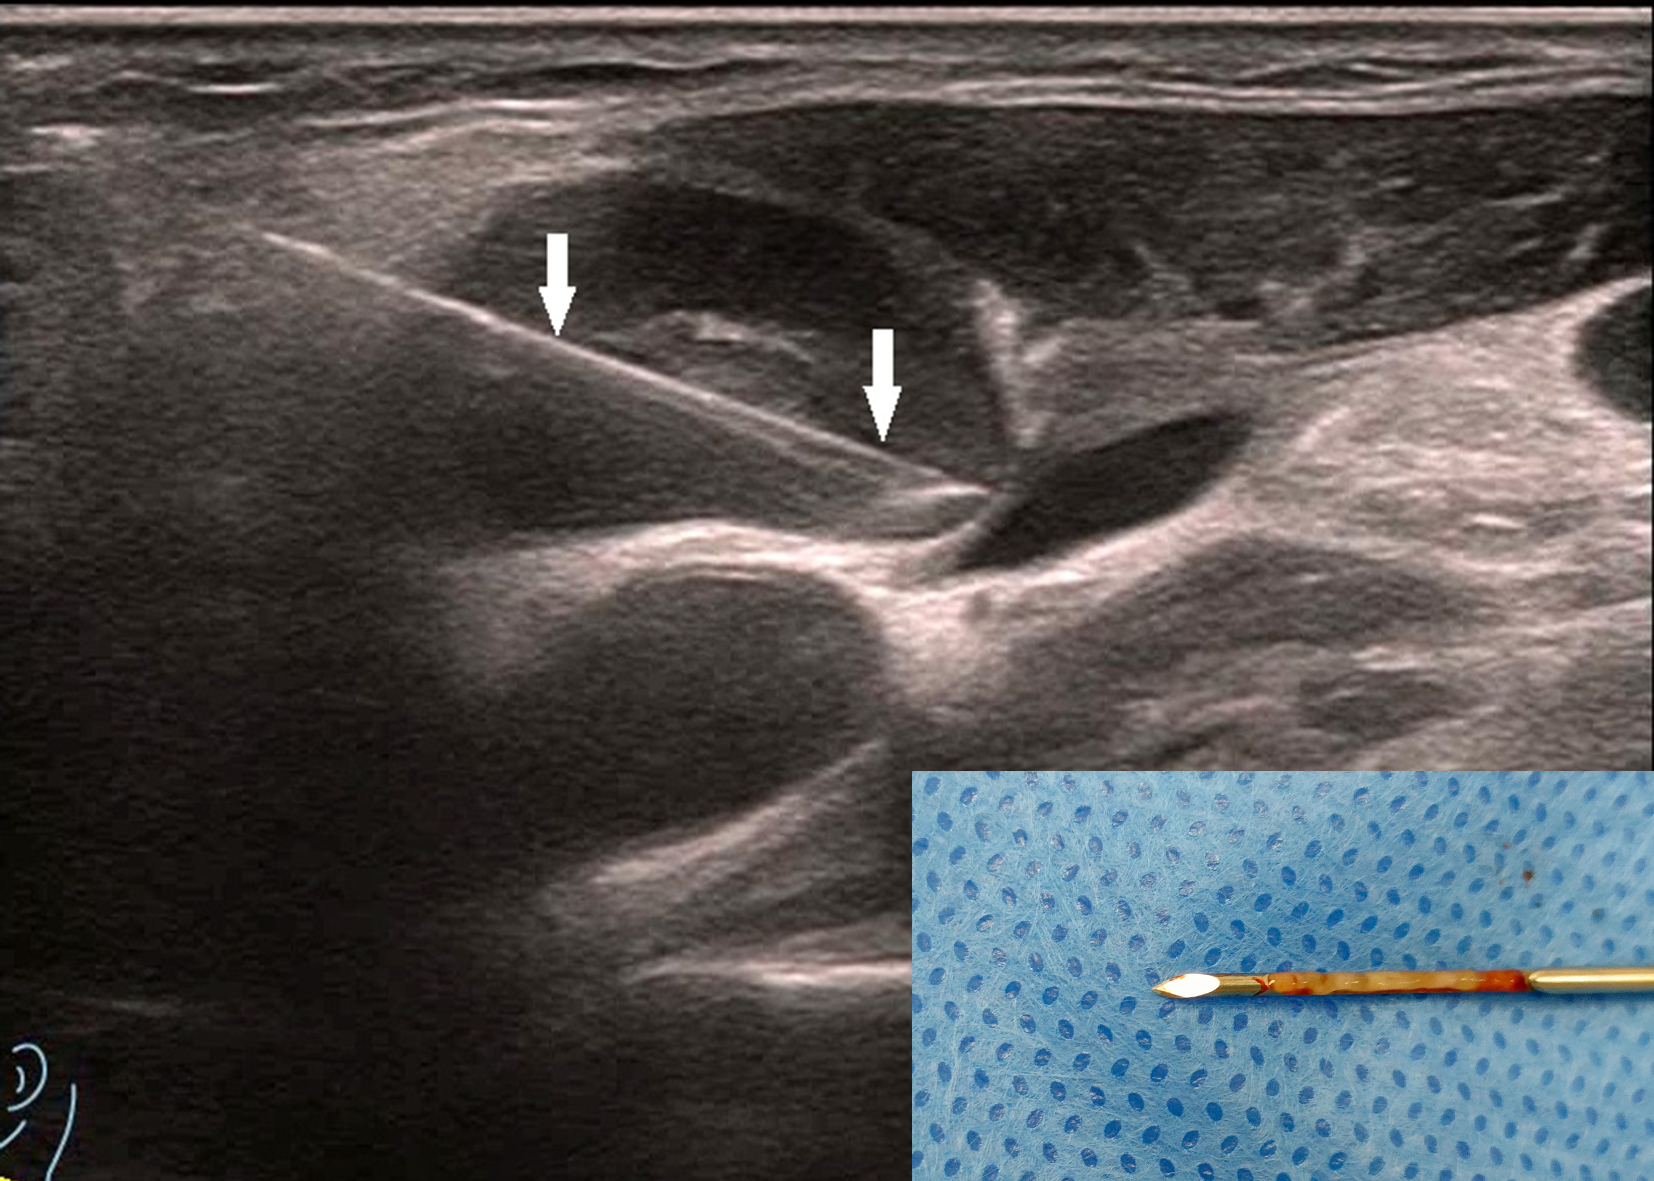

Figure 2

The patient is the same as shown in Figure 1. The target area for core needle biopsy (CNB) was the enhancement area, and the arrow shows the CNB needle. The figure on the right shows the good integrity of the puncture specimen. The patient was pathologically confirmed to have lymph node tuberculosis by Xpert MTB/RIF (+), The pathological results showed granulomatous inflammation with necrosis, suggesting tuberculosis.